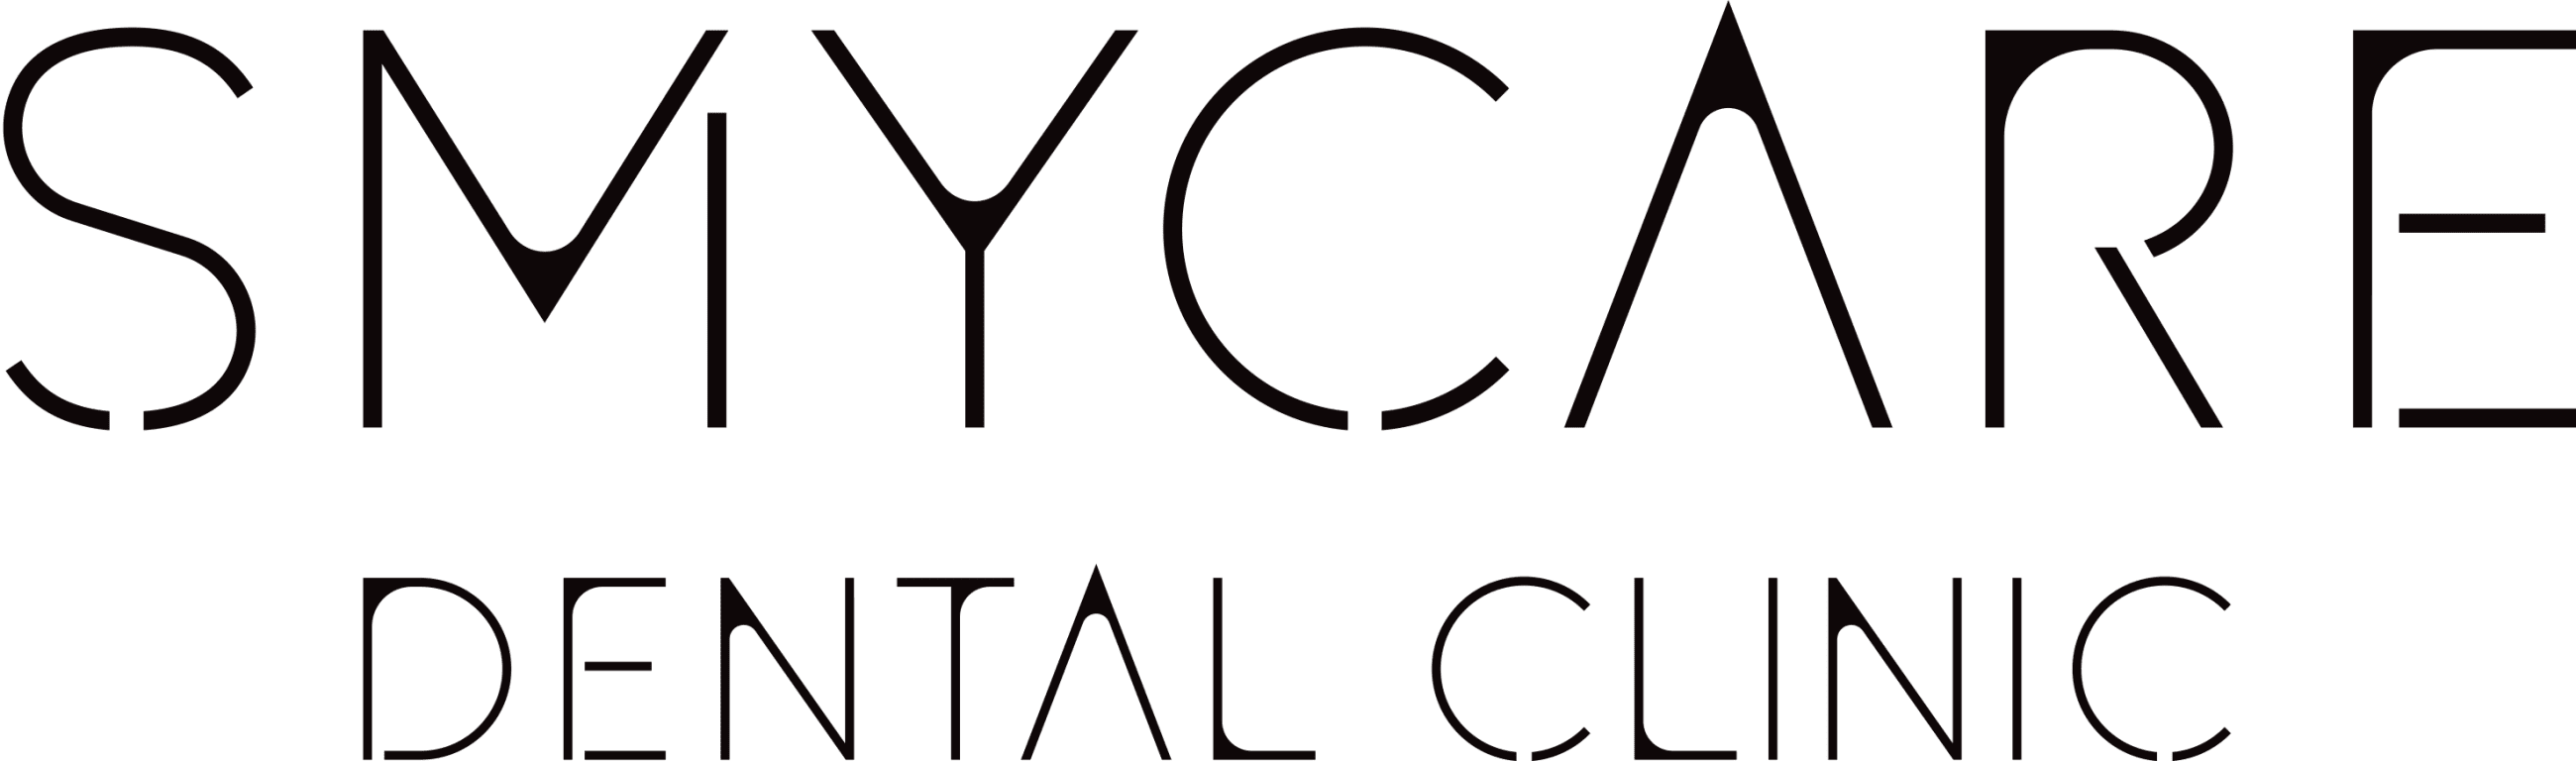

Bloková sanace kazů II. Kvadrantu (nahoře vlevo)

Bloková sanace podkažených amalgamových výplní I. Kvadrantu (nahoře vpravo)